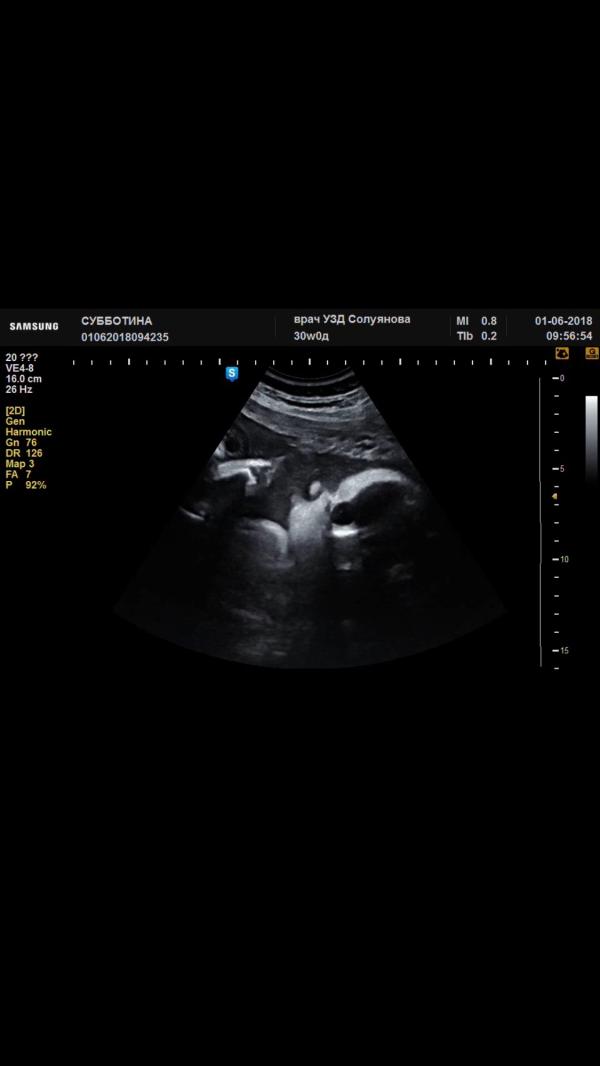

@matveeva_ka, у нас она все личико руками закрывала не давала сфотографировать, это я из видио более менее четкое нашла 😀

Классно💗у нас не одного фото с узи нет,всю беременность не могли поймать её,пол то узнали перед родами в 37 недель🤣